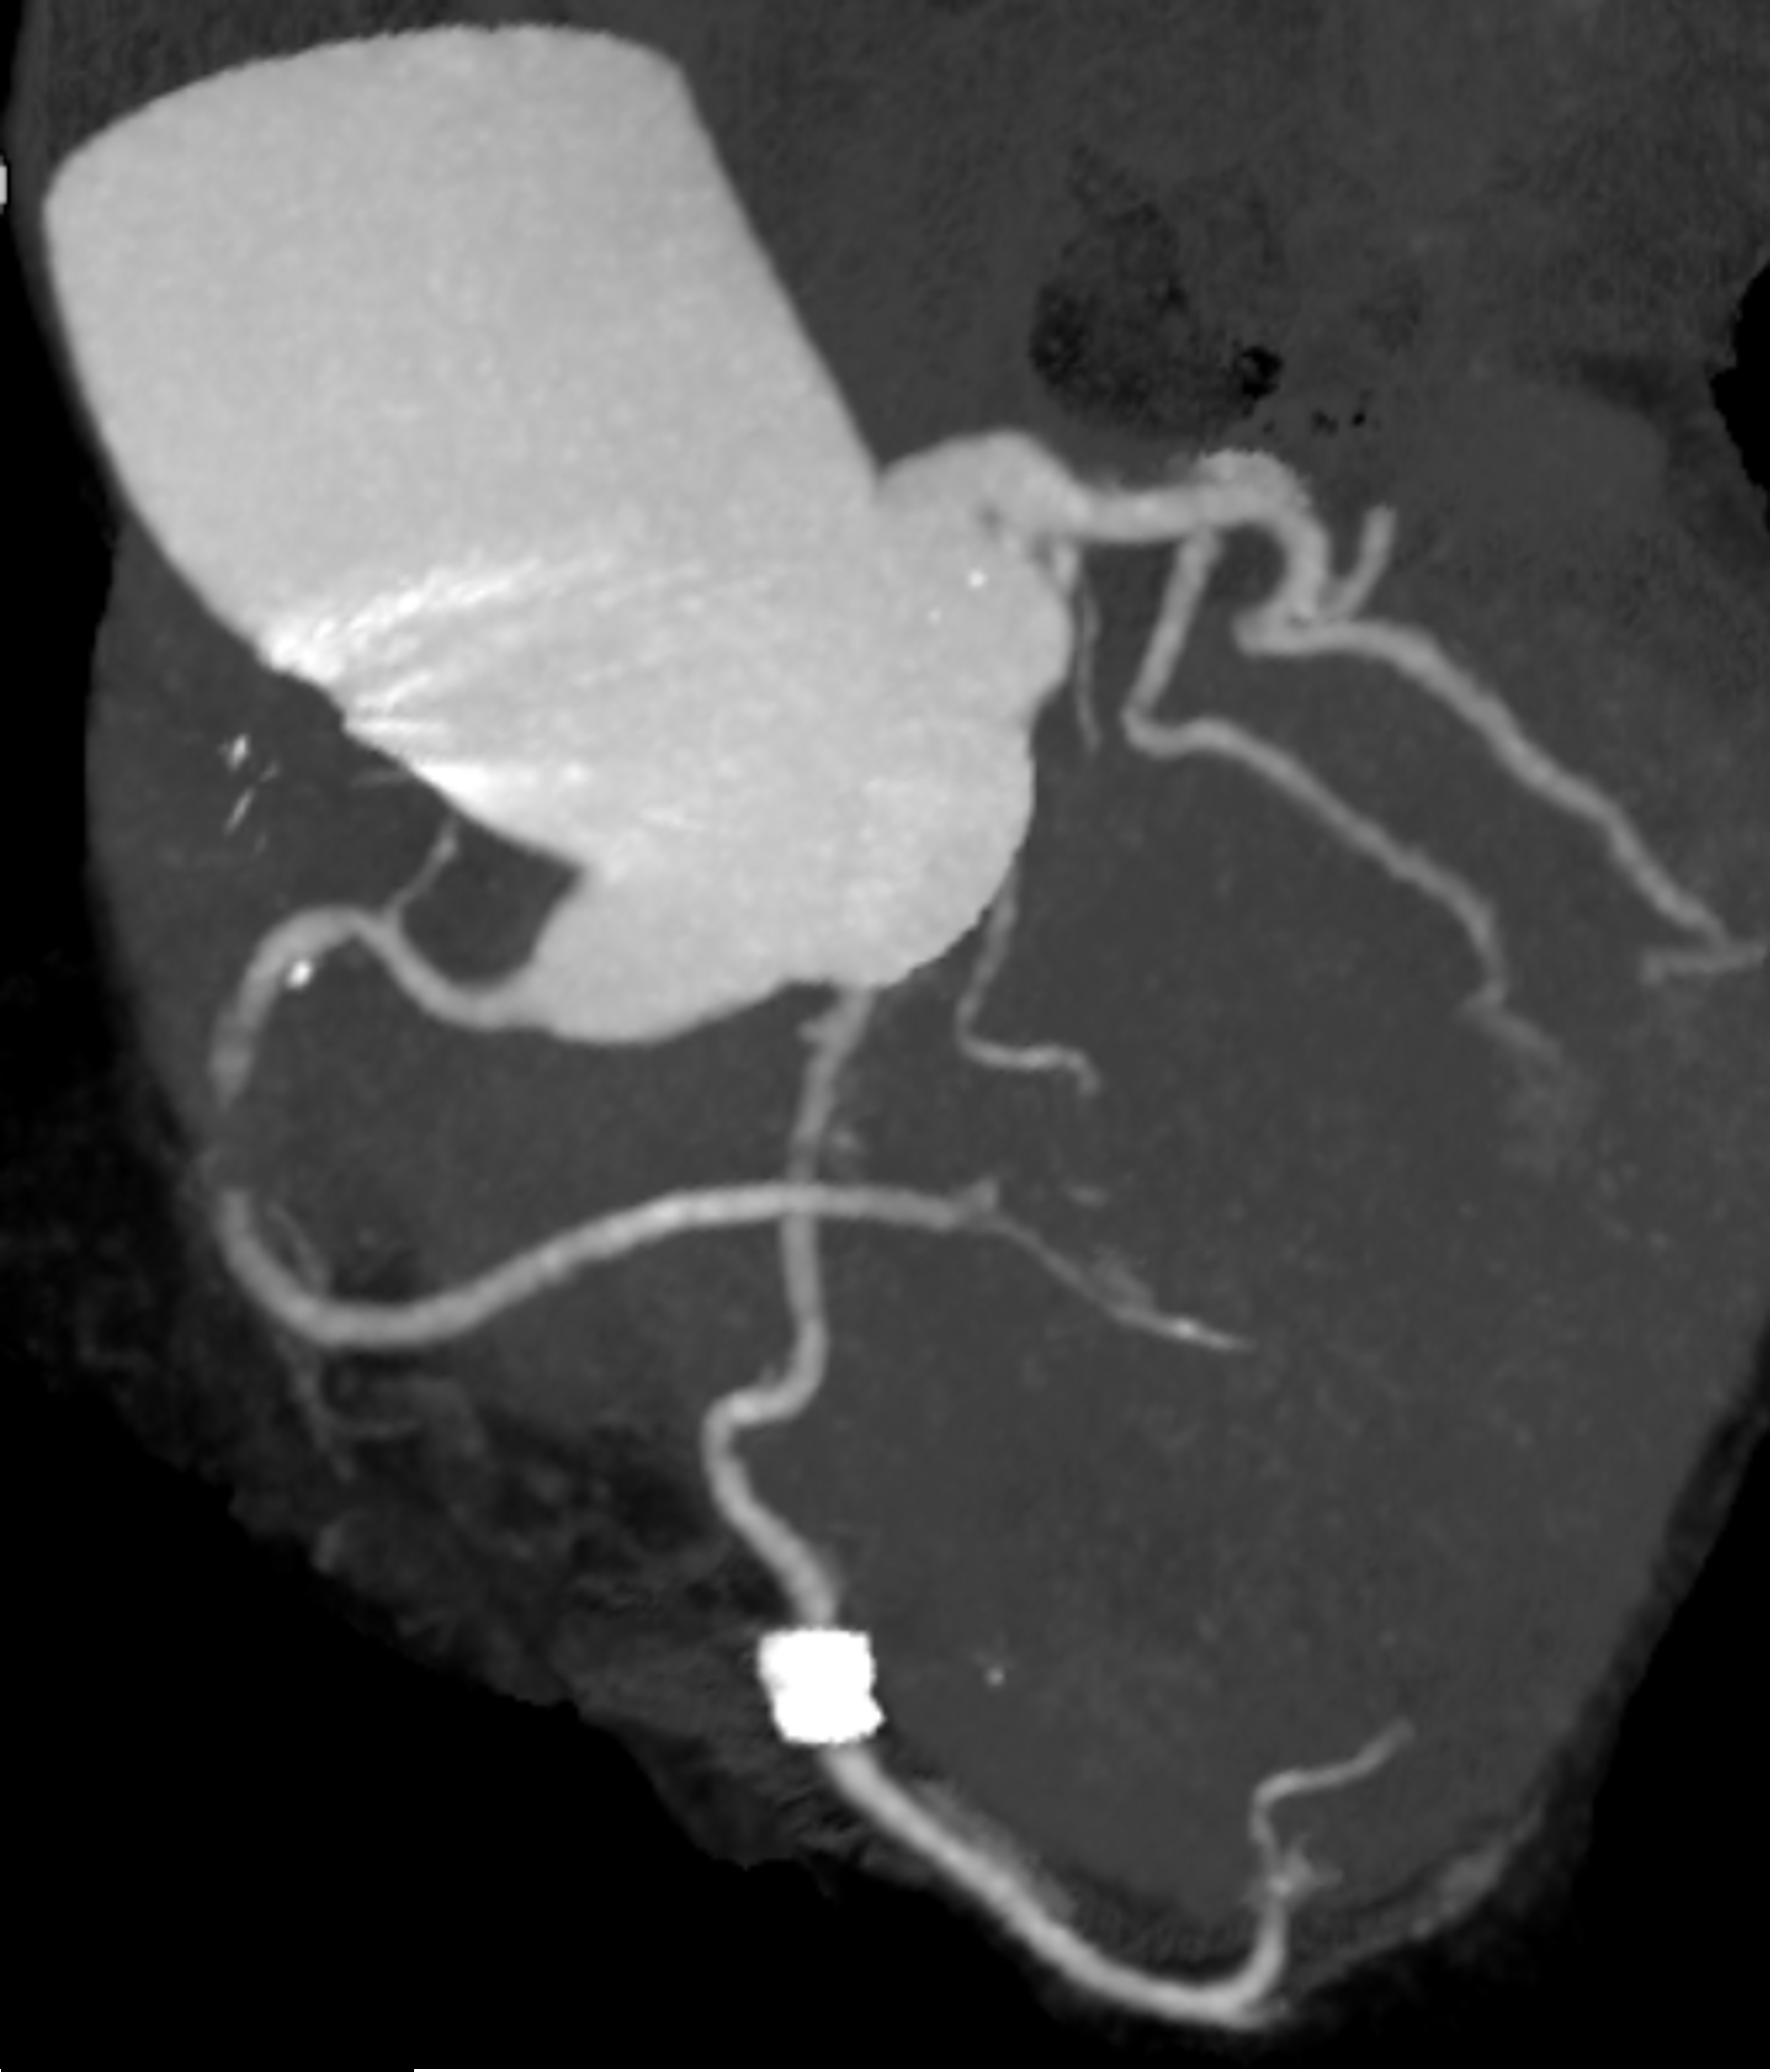

The patient was an 80-year-old woman with ahypertension, dyslipidemia, and permanent pacemaker implantation for completeatrioventricular block. She presented to another hospital with resting chestpain. The coronary computed tomography revealed severe stenosis or occlusion inthe right coronary artery (RCA), and she was referred to our hospital with adiagnosis of unstable angina.

An urgent coronary angiography showed an occlusionin the middle-part of the RCA. Rentrop grade 3 collateral arteries from theleft coronary artery to the distal RCA were observed.

A 7Fr guiding catheter (GC) was insertedvia the right femoral artery. The lesion was crossed using a floppy wire, and intravascularultrasound (IVUS) revealed a severe stenosis caused by a non-calcified plaque.The lesion was dilated using a scoring balloon. Subsequent IVUS showed an intimaldissection at the RCA ostium. To cover the initial dissection, a drug-elutingstent was deployed from the RCA ostium, followed by post-dilation with a 3.75mmnon-compliant balloon (NCB) inside the stent. IVUS demonstrated proximal stentelongation with approximately 5 mm aortic protrusion from the RCA ostium. Stentpush from the aorta using a 5.0 mm NCB, however, the GC was crushed due toinsufficient backup support. The recrossed wire passed through the side of thestent struts, and even with the knuckle wire technique, it could not beadvanced through the central lumen of the stent. IVUS was advanced thorough thiswire, and another floppy wire was successfully reinserted into the stent fromthe stent edge using the tip detection method. Another wire was placed in theRCA using a double-lumen catheter, and the anchor balloon technique wasperformed in the middle-part of the RCA with a 3.75mm NCB. Then, the stent pushtechnique was performed using a 5.0 mm NCB to shorten the elongated stent,followed by post-dilation of the proximal stent with the 3.75mm NCB. IVUSconfirmed successful stent shortening, with approximately 1.2mm of stentprotrusion into the aorta, which was acceptable.